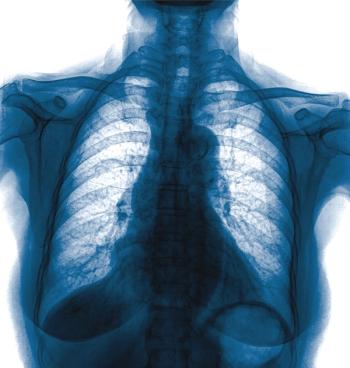

Radiologists in the United Kingdom are now using radiography to speed up COVID-19 identification.

ACR recommends against using CT as a first-line test; offers advice on imaging use.

Chest CTs and X-rays highlight characteristics of EVALI in teens.

Patients with the coronavirus who develop pneumonia exhibit similar findings on chest CT scans.